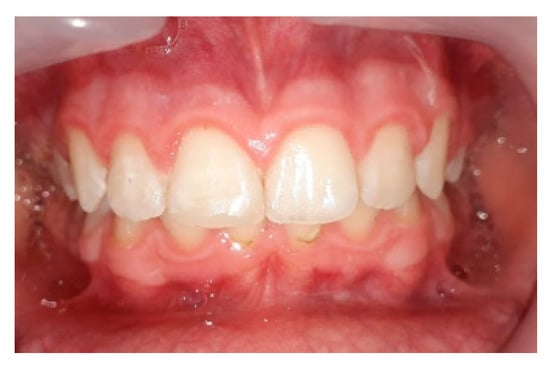

3.1. Outcomes of the Treatment at the One-Year Follow-Up

3.2. Cephalometric Values after One Year of Treatment

3.3. Situation of the Treatment after Two Years